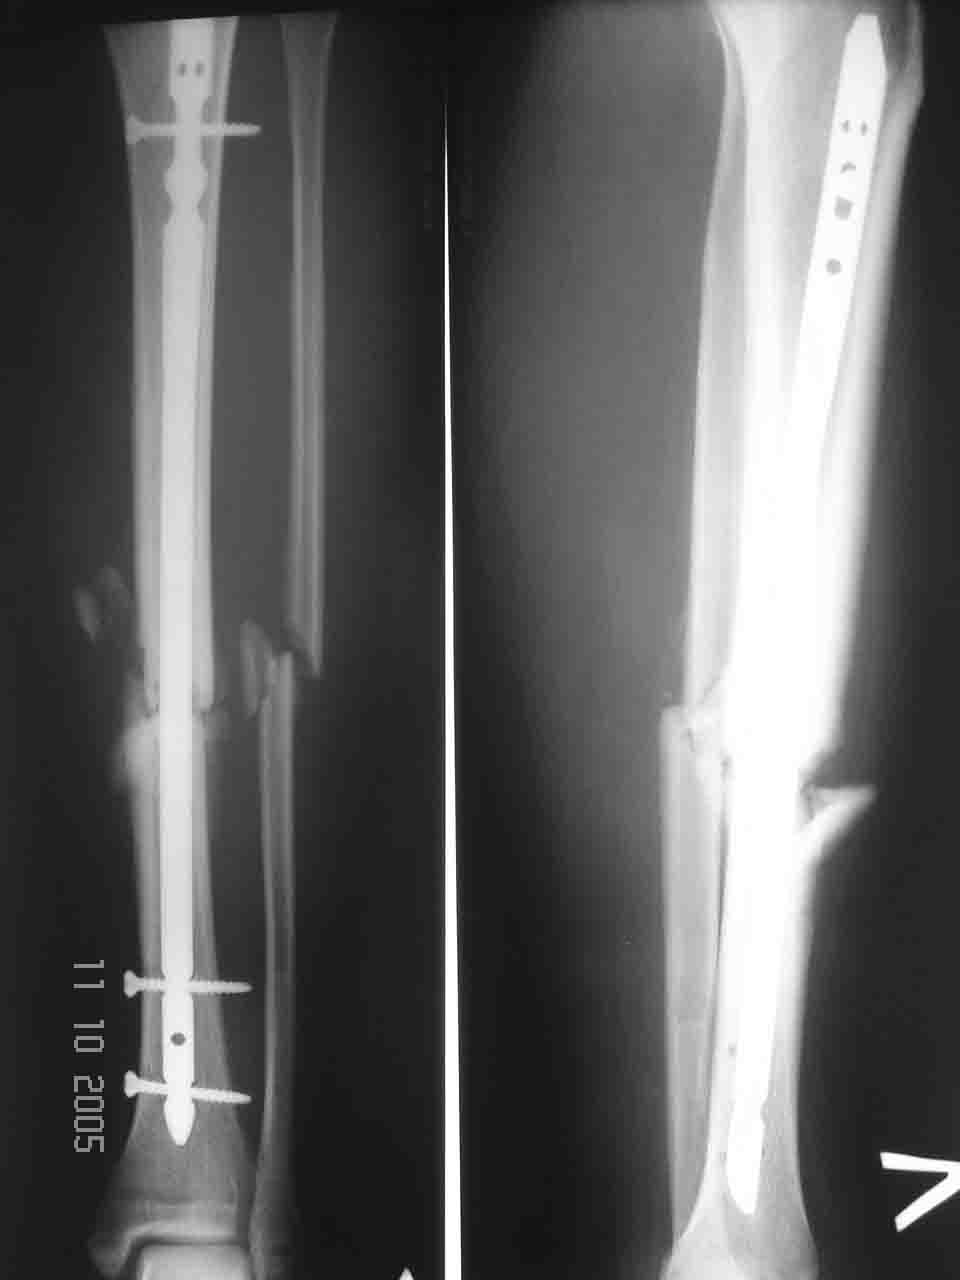

Что-то рано сломалась пластина - в чем видите причину?

Уважаемый Алексей, глядя на Р-граммы левой голени фиксированной пластиной создается впечатление, что имеется дефект б/берцовой кости. Учитывая это при ЧКО необходимо выполнить костную пластику дефекта. В противном случае кость даже после консолидиции останется слабой, что приведет к повторному перелому. Мне кажется, что в данном случае предпочтителен ЗИО б\берцовой кости с рассверливанием костномозгового канала и блокированием, т.к. при ЗИО активизируются процессы регенерации за счет гематомы в области перелома, что приводит к образованию параоссальной костной мозоли. Плюс к этому в кости будет находится прочный фиксатор, который очень редко ломается и не беспокоит пациента.

Перелом пластины наступил, по нашему мнению, вследствии проведенного нестабильного остеосинтеза (необходимо было выполнить накостный остеосинтез с костной аутопластикой). Возможно проведение данной операции и в настоящее время, то есть при удалении сломанной пластины вновь выполнить стабильный накостный остеосинтез с костной аутопластикой.

Ни в одном, ни в другом случае иммобилизация выбрана неправильно. "на шипе" сращения ждать долго и, извините, глупо. Тем более, что отломки сопоставлены крайне плохо. Иммобилизация и пластиной и стержнем (по рентгенограммам видно)нестабильны. Удалите пластину и интрамедулярную конструкцию и произведите иммобилизацию аппаратами внешней фиксации. Ведь еще Илизаровым доказано, что для голеней лучшей фиксации, чем АВФ нет.

Причина перелома - на мой взгляд - неадекватная репозиция. Сегмент удлинен, об этом говорит диастаз между отломками малоберцовой кости. Отсюда и впечатление "дефекта". Он есть, но вторичен.